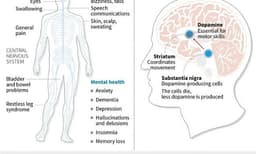

Other less obvious causes of mid-life pain include sleep apnoea, characterized by disrupted breathing during sleep, which can lead to increased pain sensitivity and issues in the neck, jaw, and shoulders. Parkinson's disease, which can affect working-age individuals, may initially present with stiffness and muscle aches. Even dehydration can contribute to joint stiffness and headaches by reducing essential lubricating fluids.